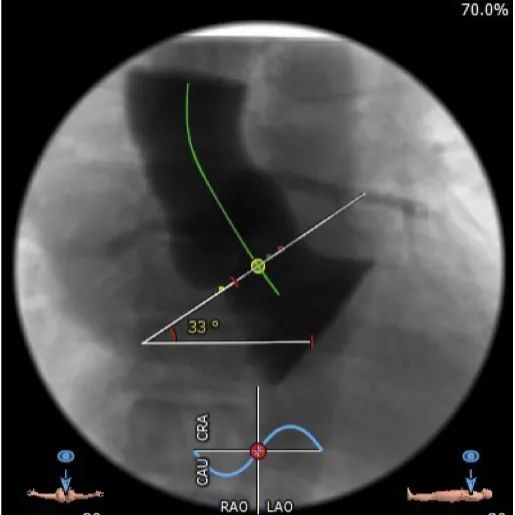

升主动脉未见明显扩张,心脏角度:33°。